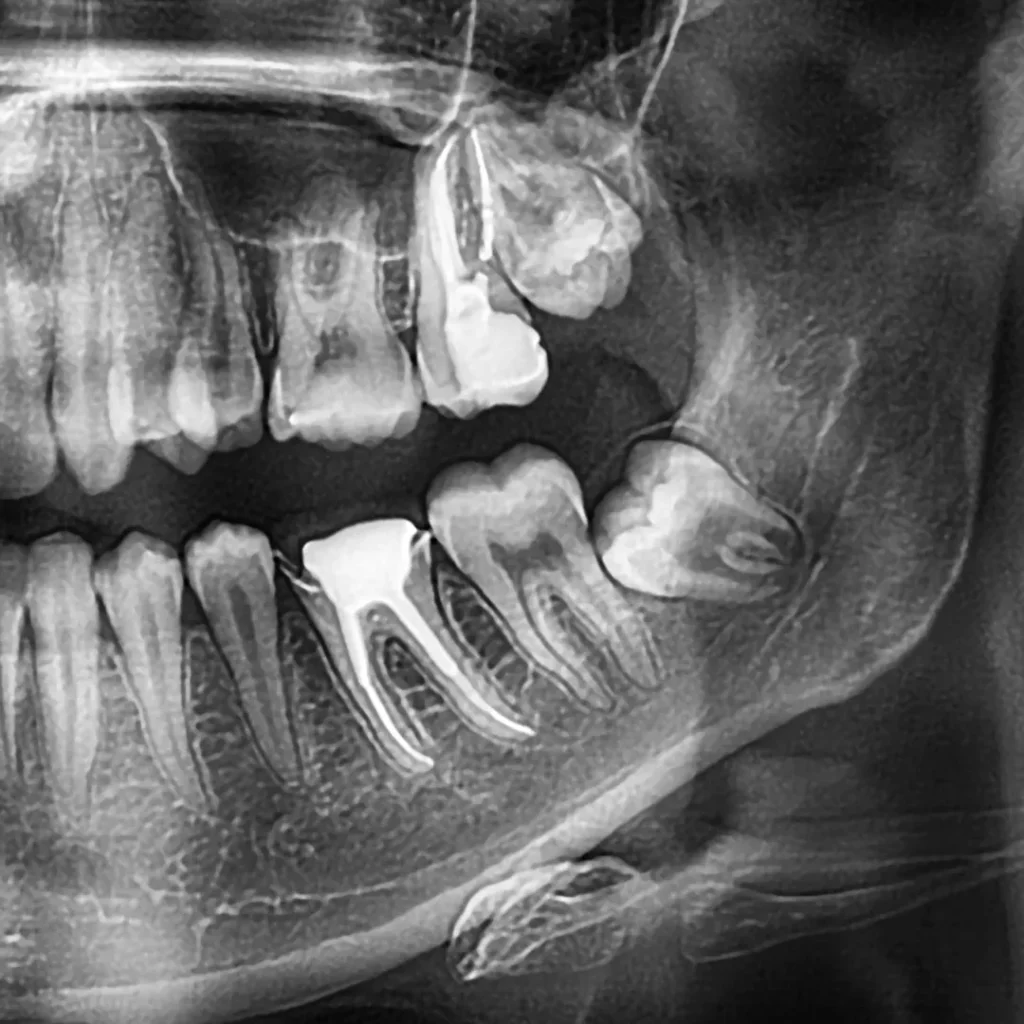

Wisdom Tooth Extractions

Gentle and safe removal of impacted or problematic wisdom teeth to prevent pain, infection, and crowding.

Wisdom teeth often grow in at awkward angles or become impacted, leading to swelling, pain, and infection. Our Upper East Side oral surgeons perform precise, gentle extractions using local anesthesia for your comfort. Most patients recover quickly with minimal downtime when post-operative care instructions are followed.